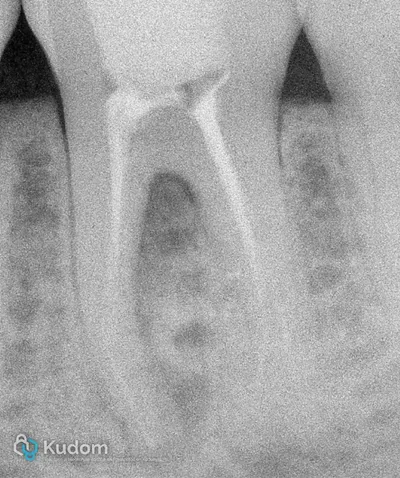

Ritrattamento endodontico complesso di un primo molare inferiore con lesione alla forcazione e otturazione di un canale laterale con successivo build-up per overlay a ricopertura cuspidale.

Ritrattamento di un molare inferiore con gestione di perforazione iatrogena a livello della forcazione, sotto l'imbocco radicolare.